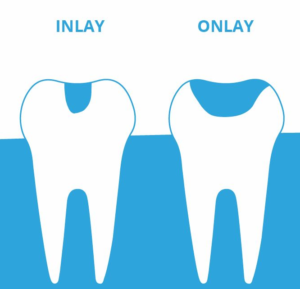

Inlays & Onlays